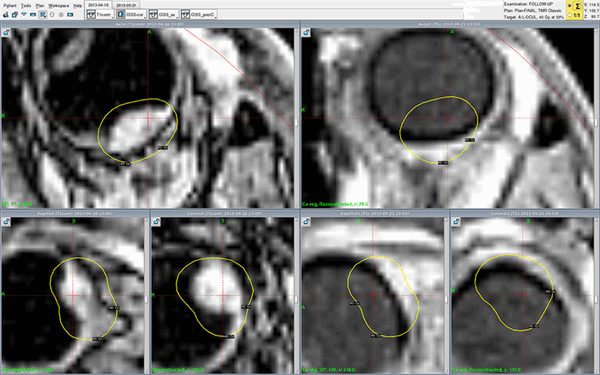

Примеры меланоцитомы цилиарного тела

Реальный клинический случай - лечение меланомы хориоидеи Гамма-ножом Gamma-Knife Perfexion в Онкологической клинике МИБС. Снимки МРТ с контрастом (слева - до, справа - после лечения). Меланома хориоидеи на правом снимке, сделанном во время контрольного обследования всего через один месяц (!), не визуализируется - желтые контуры изначального расположения опухоли нанесены для сравнения. Опухоль исчезла. Без операции, с сохранением глазного яблока.